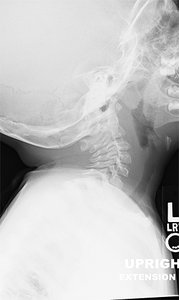

Review the cervical flexion radiograph in Figure 1A. The patient has an increased atlantodental interval (ADI) at C1-C2. Now review the cervical extension radiograph of the same patient in Figure 1B. The ADI decreased. Why?

Figure 1B